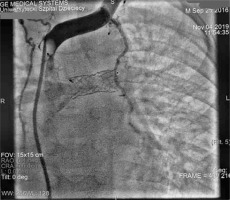

Cardiac catheterisation revealed a significant collateral vessel from the left inferior thyroid artery supplying the left lung and additional collateral vessels arising from the left (LIMA) and right (RIMA) internal mammary arteries supplying both lungs (Figure 1). The Fontan tunnel measured 14.1 mm at its junction with the IVC, widening centrally to 26 mm, and tapering to 10.9 mm at the junction with the pulmonary arteries. No fenestration was identified. The stent in the left pulmonary artery measured 9.8 mm proximally, increasing to 11.2 mm distally (Figure 2). During the procedure, an Amplatzer Vascular Plug successfully occluded the collateral vessel from the left inferior thyroid artery to the left lung, and vascular coils were placed in the RIMA and LIMA. Additionally, a 6-mm Valeo stent was implanted to create a new fenestration (Figure 3).

Figure 1

Angiogram of the left brachio-cephalic vein. The plug is inserted into the left mammary artery. Wide left brachio-cephalic artery (innominate artery), and the collateral vessel to the left lung (asterisk) are visible. A stent was placed in the left pulmonary artery